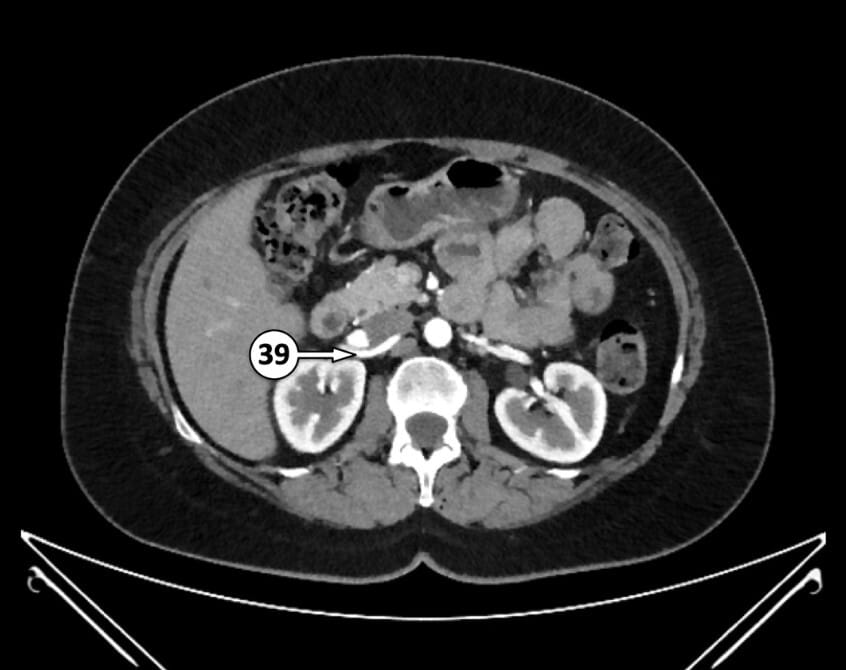

39. right renal artery